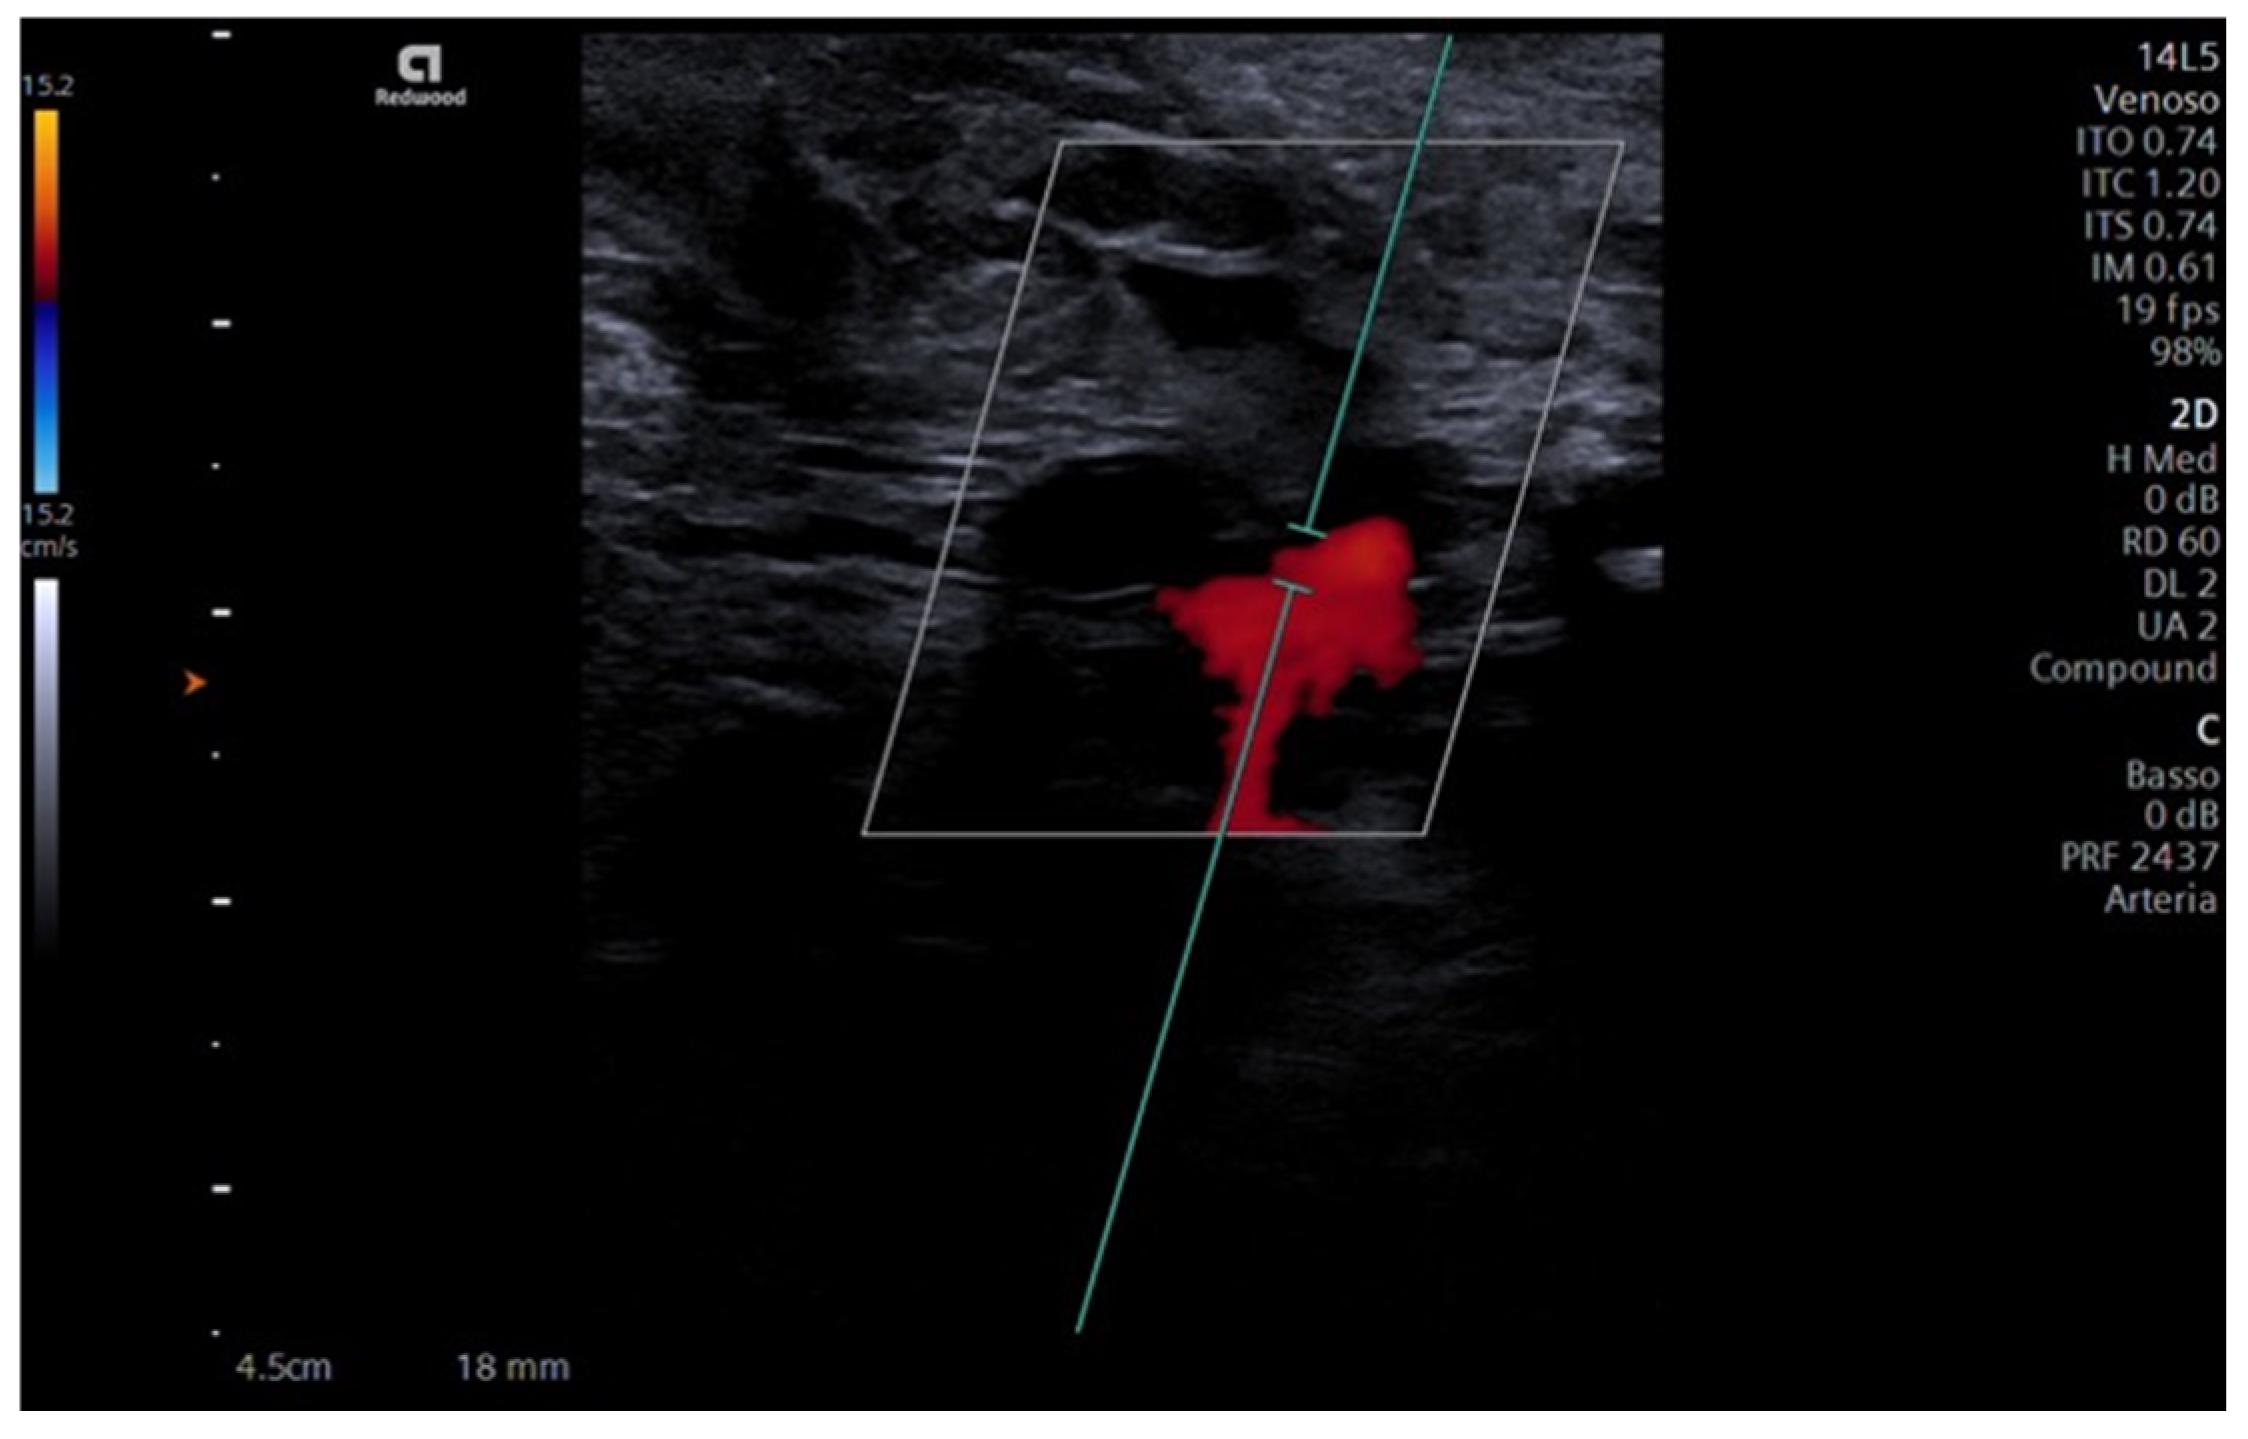

Furthermore, blood flow presence and entity in the neoanastomosis were recorded using doppler ultrasound, with favorable outcomes (Figure 5).

Ultrasound with Color-Doppler can be useful to evaluate the success of the procedure [36]; however, micro-bubbles inherently present in the artificial blood generate minor artifacts, as shown in Figure 5, and further studies are needed to optimize the scanning settings to improve the quantitative evaluation in this context.

Figure 5. Doppler ultrasound. The figure shows the Color-Doppler ultrasound evidencing blood-mimicking fluid presence in the anastomosis between superficial temporal and facial arteries.